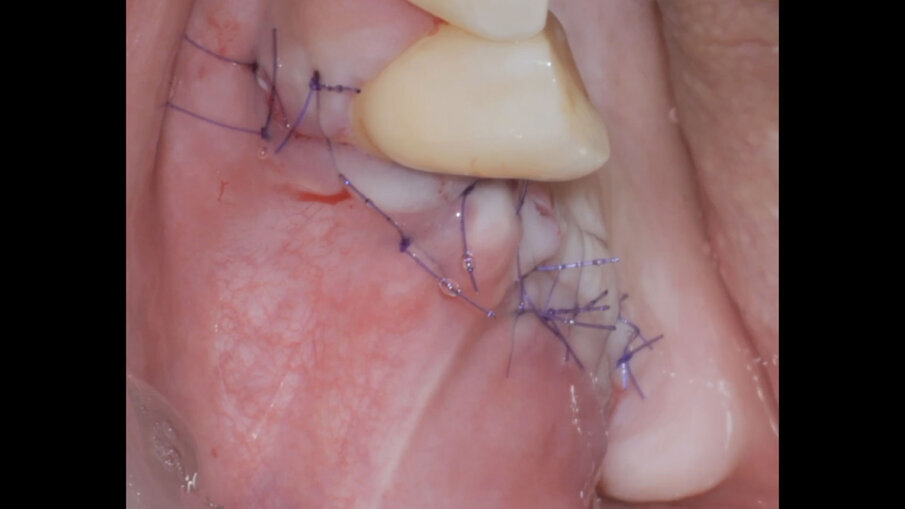

La procedura termina con il rilascio del lembo vestibolare, una seconda applicazione di Regenfast sulla superficie della membrana stabilizzata, la chiusura dei lembi per prima intenzione mediante una combinazione di punti a materassaio interno e punti staccati, ed una terza applicazione di Regenfast al di sopra della linea di chiusura (Figg. 5, 6). Dimessa la paziente in stato vigile e orientato, con coagulo competente, si rimuove la sutura a distanza di 14 giorni, riscontrando un decorso post-chirurgico nella norma (Fig. 7).

Fig. 5 - Applicazione stratificata di Regenfast durante la tecnica GBR.

Fig. 6 - Chiusura del lembo ed applicazione finale di Regenfast sulla linea di sutura.